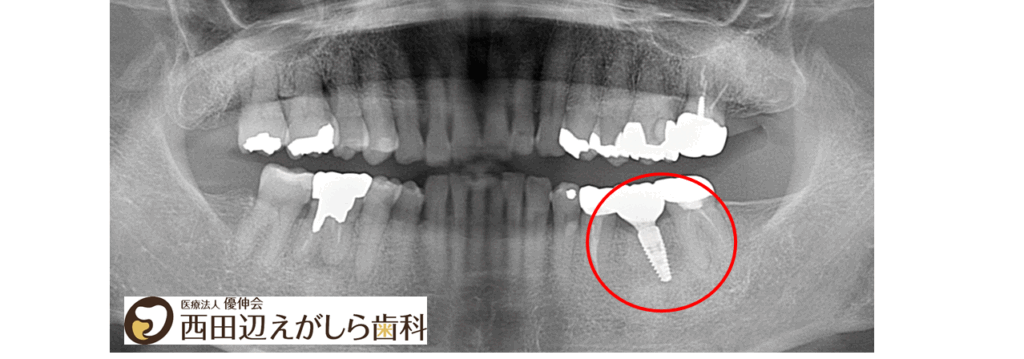

まず抜歯を行い、約1か月ほど経過をみて、抜歯部位の治癒を待ちました。その後、静脈内鎮静法を併用しながらインプラント埋入手術を行いました。抜歯後間もない時期で骨の回復途中でもあったため、必要に応じて骨補填材やCGFを併用し、周囲組織の状態にも配慮しながら治療を進めました。

インプラント埋入後は、約3か月の治癒期間を設け、インプラントが骨としっかり結合していることを確認しました。その後、口腔内スキャナーを用いて上部構造製作のためのスキャニングを行い、最終的な被せ物を装着しました。